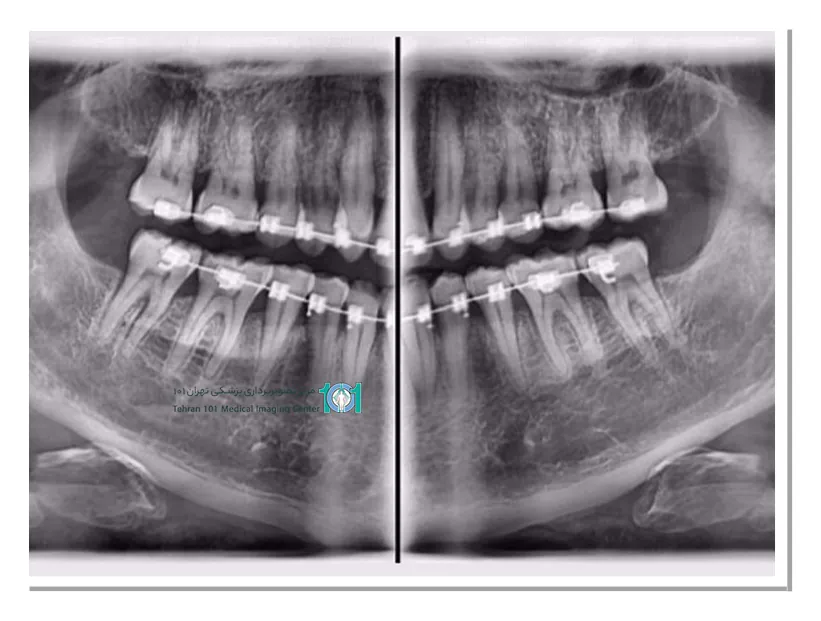

توموگرافی ساده و کامپیوتری (CT): توموگرافی ساده تصاویر دوبعدی را ارائه میدهد و به آن رادیوگرافی سنتی داخل دهانی یا پانورامیک نیز گفته میشود.

ارتودنسی: درصورتیکه برای ارتودنسی و درمان ناهنجاریهای فک و صورت نیاز به ارزیابی توسط متخصص رادیولوژی فک و صورت وجود دارد، دندانپزشک ممکن است شما را به او ارجاع دهد.